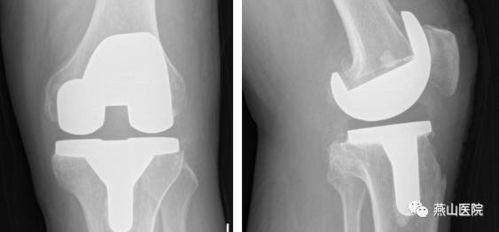

膝关节置换视频,从术前准备到术后康复

你有没有想过,当你的膝关节像老化的弹簧一样“嘎吱嘎吱”作响时,是不是该考虑一下换一个全新的“关节”呢?没错,我说的就是膝关节置换手术。今天,就让我带你一起走进这个神秘的世界,通过膝关节置换视频,看看这个手术的全过程,...